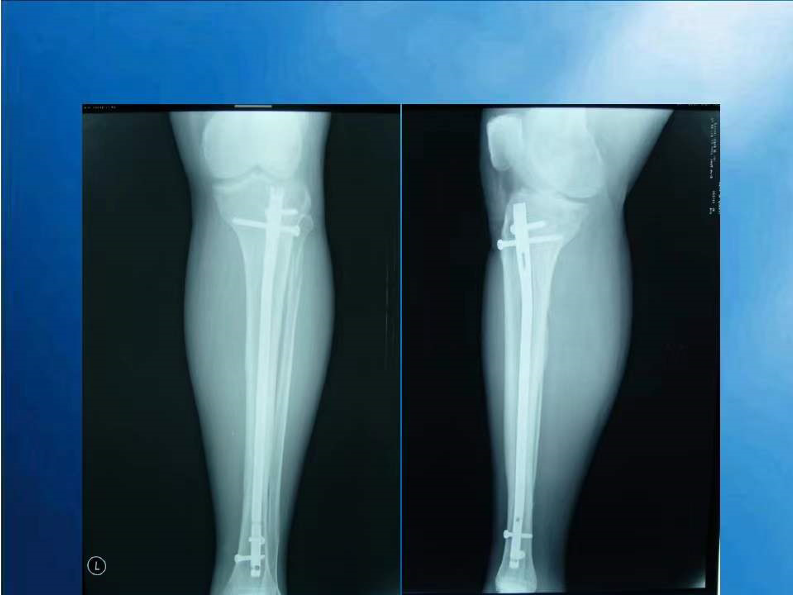

胫腓骨骨折